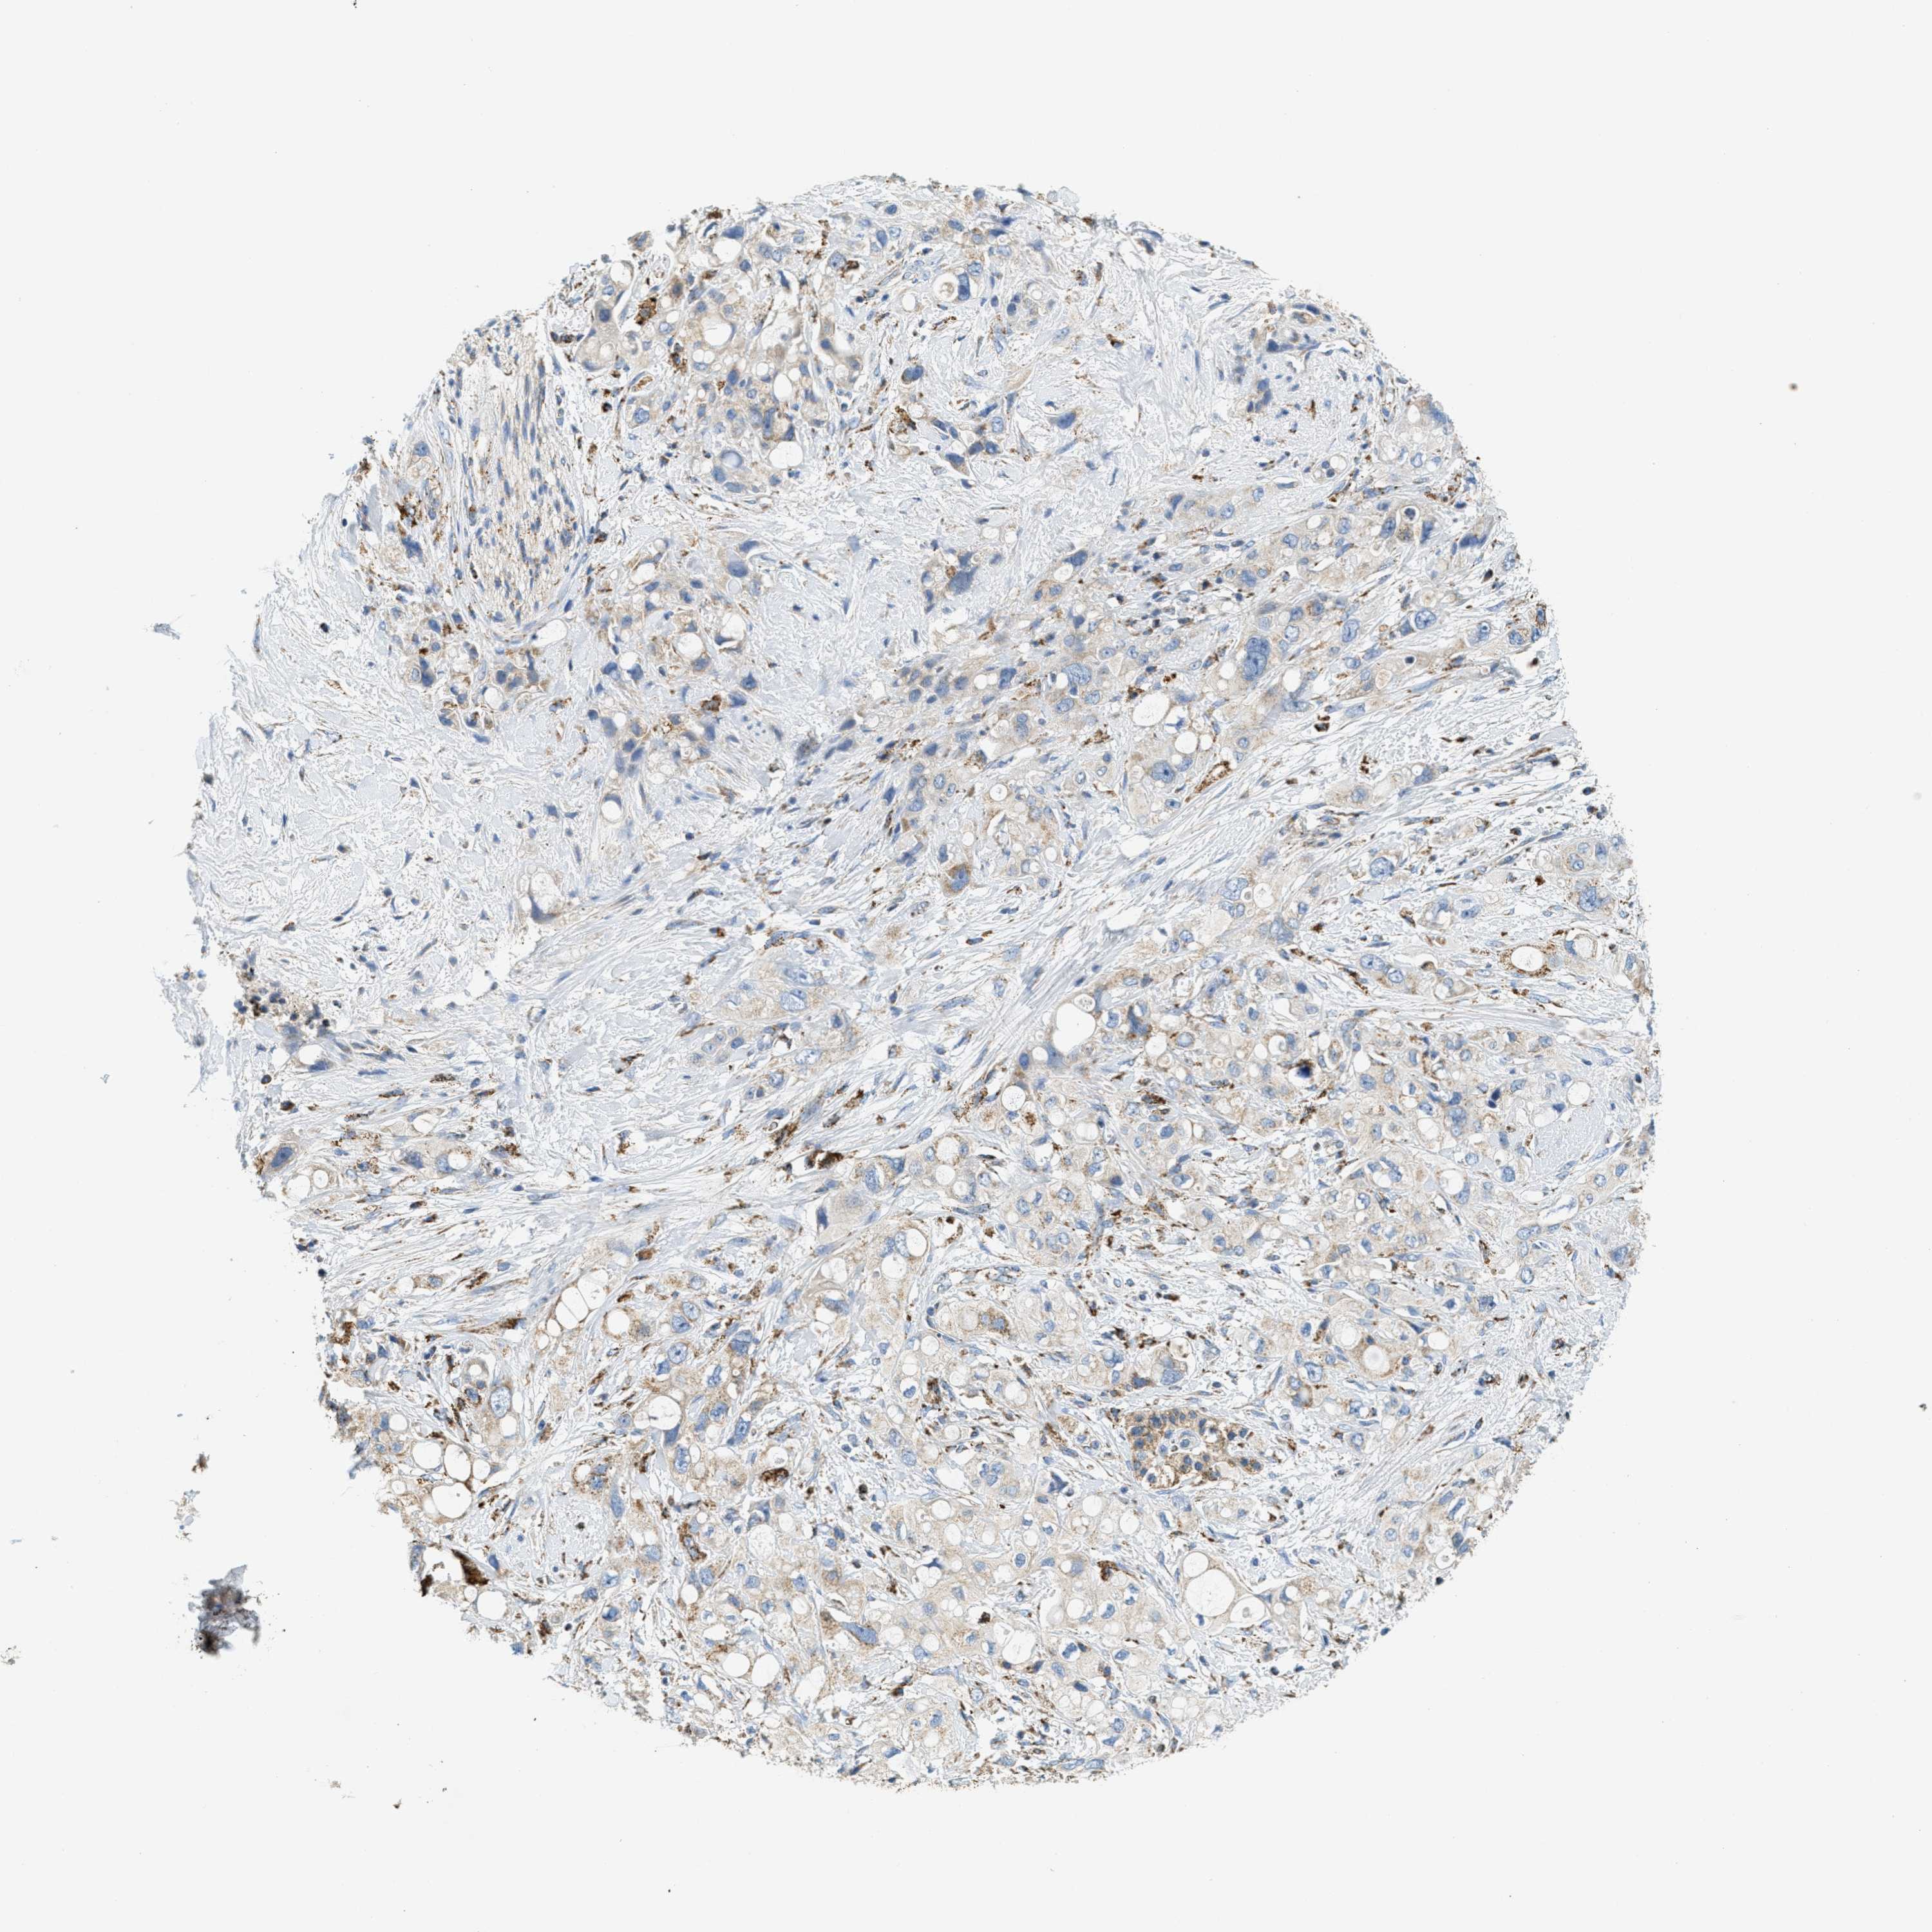

PANCREATIC CANCER - Protein expressioni

A mouse-over function shows sample information and annotation data. Click on an image to view it in a full screen mode. Samples can be filtered based on level of antibody staining by selecting one or several of the following categories: high, medium, low and not detected. The assay and annotation is described here.

Note that samples used for immunohistochemistry by the Human Protein Atlas do not correspond to samples in the TCGA dataset.

Antibody stainingi

Antibody staining in the annotated cell types in the current human tissue is reported as not detected, low, medium, or high, based on conventional immunohistochemistry profiling in selected tissues. This score is based on the combination of the staining intensity and fraction of stained cells.

Each image is clickable and will lead to virtual microscopy that enables deeper exploration of all samples and also displays staining intensity scores, fraction scores and subcellular localization as well as patient and tissue information for each sample.

Antibody HPA017379

Staining

High

Medium

Low

Not detected

Intensity

Strong

Moderate

Weak

Negative

Quantity

>75%

75%-25%

<25%

None

Location

Nuclear

Cytoplasmic/membranous

Cytoplasmic/membranous,nuclear

Adenocarcinoma, NOS